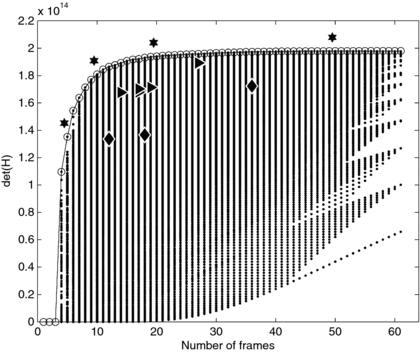

Standard image High-resolution imageThe experiment design in figure 3(c) is one of many considered in the exhaustive search process. Figure 4 shows the det(H) calculated for the range of the exhaustive search. Among each column of points, which represents a fixed number of frames, the top-most point has the highest det(H) and is the optimal design for that number of frames. We found that for any number of frames, the optimal schedule gave a higher det(H) than any optimal schedule with fewer frames. The more-optimal schedules tend to have several short frames clustered early, when the signal is changing rapidly and near the sensitivity functions' maxima, and longer frames at later times, following the overall pattern seen in figures 3(b) and (c). As examples, the optimal schedules for 5, 10, 20 and 50 total frames are noted in figure 4 by stars. Those schedules are

.

| 5 frames: | 1 × 5s | + | 1 × 20s | + | 2 × 60s | + | 1 × 215s |

| 10 frames: | 2 × 3s | + | 3 × 10s | + | 4 × 60s | + | 1 × 84s |

| 20 frames: | 4 × 2s | + | 6 × 5s | + | 9 × 30s | + | 1 × 52s |

| 50 frames: | 20 × 1s | + | 14 × 2s | + | 15 × 20s | + | 1 × 12s |

We then compared det(H) for our optimized schedules to experiment schedules described in literature. The schedules described in literature are described in table 2 and indicated in figure 4 by triangles. In all cases our design optimization was able to determine sampling schedules that improved the previously published schedules.

Figure 4. Values of the D-optimal criterion calculated using the exhaustive search method. The optimal schedule with each number of frames, at the top of each column of points, is circled. The schedules marked with stars are enumerated in the text. Diamonds mark examples of uniform sampling with 12, 18 and 36 frames. Triangles denote literature-derived scanning designs as detailed in table 2.